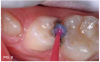

Case 2. This 2-year-old boy had mesial caries lesions of his maxillary central incisors associated with chronic plaque accumulation and lack of tooth brushing or flossing by the parents (Figure 5 and Figure 6). The parents, who were given extensive instructions to remedy the oral hygiene problem, consented to SDF application despite the black discoloration. They related that they not only wanted to avoid a repair appointment for the child, but they also liked the idea that traditional restoration could be delayed until he was older and could more easily tolerate treatment. Three months after initial SDF application, the solution was reapplied (Figure 7).

Fig 6. Much plaque accumulation; no oral home care apparent.

Fig 6

Fig 7. 3 months after SDF application, before renewed application.

Fig 7